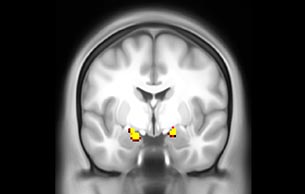

Imaging was performed using Ingenia 3T CX with a 32ch dS Head coil, TR 1.6 sec, TE 35 ms, voxel size 3.1 x 3.1 x 3.1 mm, 46 slices and Multiband SENSE factor 2. Image provided by Dr. Gispert

Default mode network as discovered by resting state fMRI in one participant of the ALFA cohort [7]. rs-fMRI allows us to find networks of brain regions with highly correlated activity and sustaining distinct brain functions. The default mode network (in warm color scale) is active when the brain is focused on introspective thinking and has been shown to be altered in Alzheimer’s. Interestingly, brain areas of this network are known to show abnormal levels of one of the pathological hallmarks of Alzheimer’s (b-amyloid deposition) in preclinical stages. We want to better understand the alterations of these brain networks in preclinical stages of Alzheimer's and explore their potential use as biomarkers.

“We perform a resting-state fMRI sequence in all individuals of the cohort. Because of the vascular dynamics of restingstate in the brain, we feel it doesn’t make sense to go to shorter acquisition. So, we use MultiBand SENSE to double the amount of scans we acquire in a fixed amount of time. We are extremely happy with the quality we get for retrieving the default mode network. In about eight minutes, we acquire 300 volumes of 46 slices with an isotropic voxel size of 3 mm and a TR of 1.6 ms.”